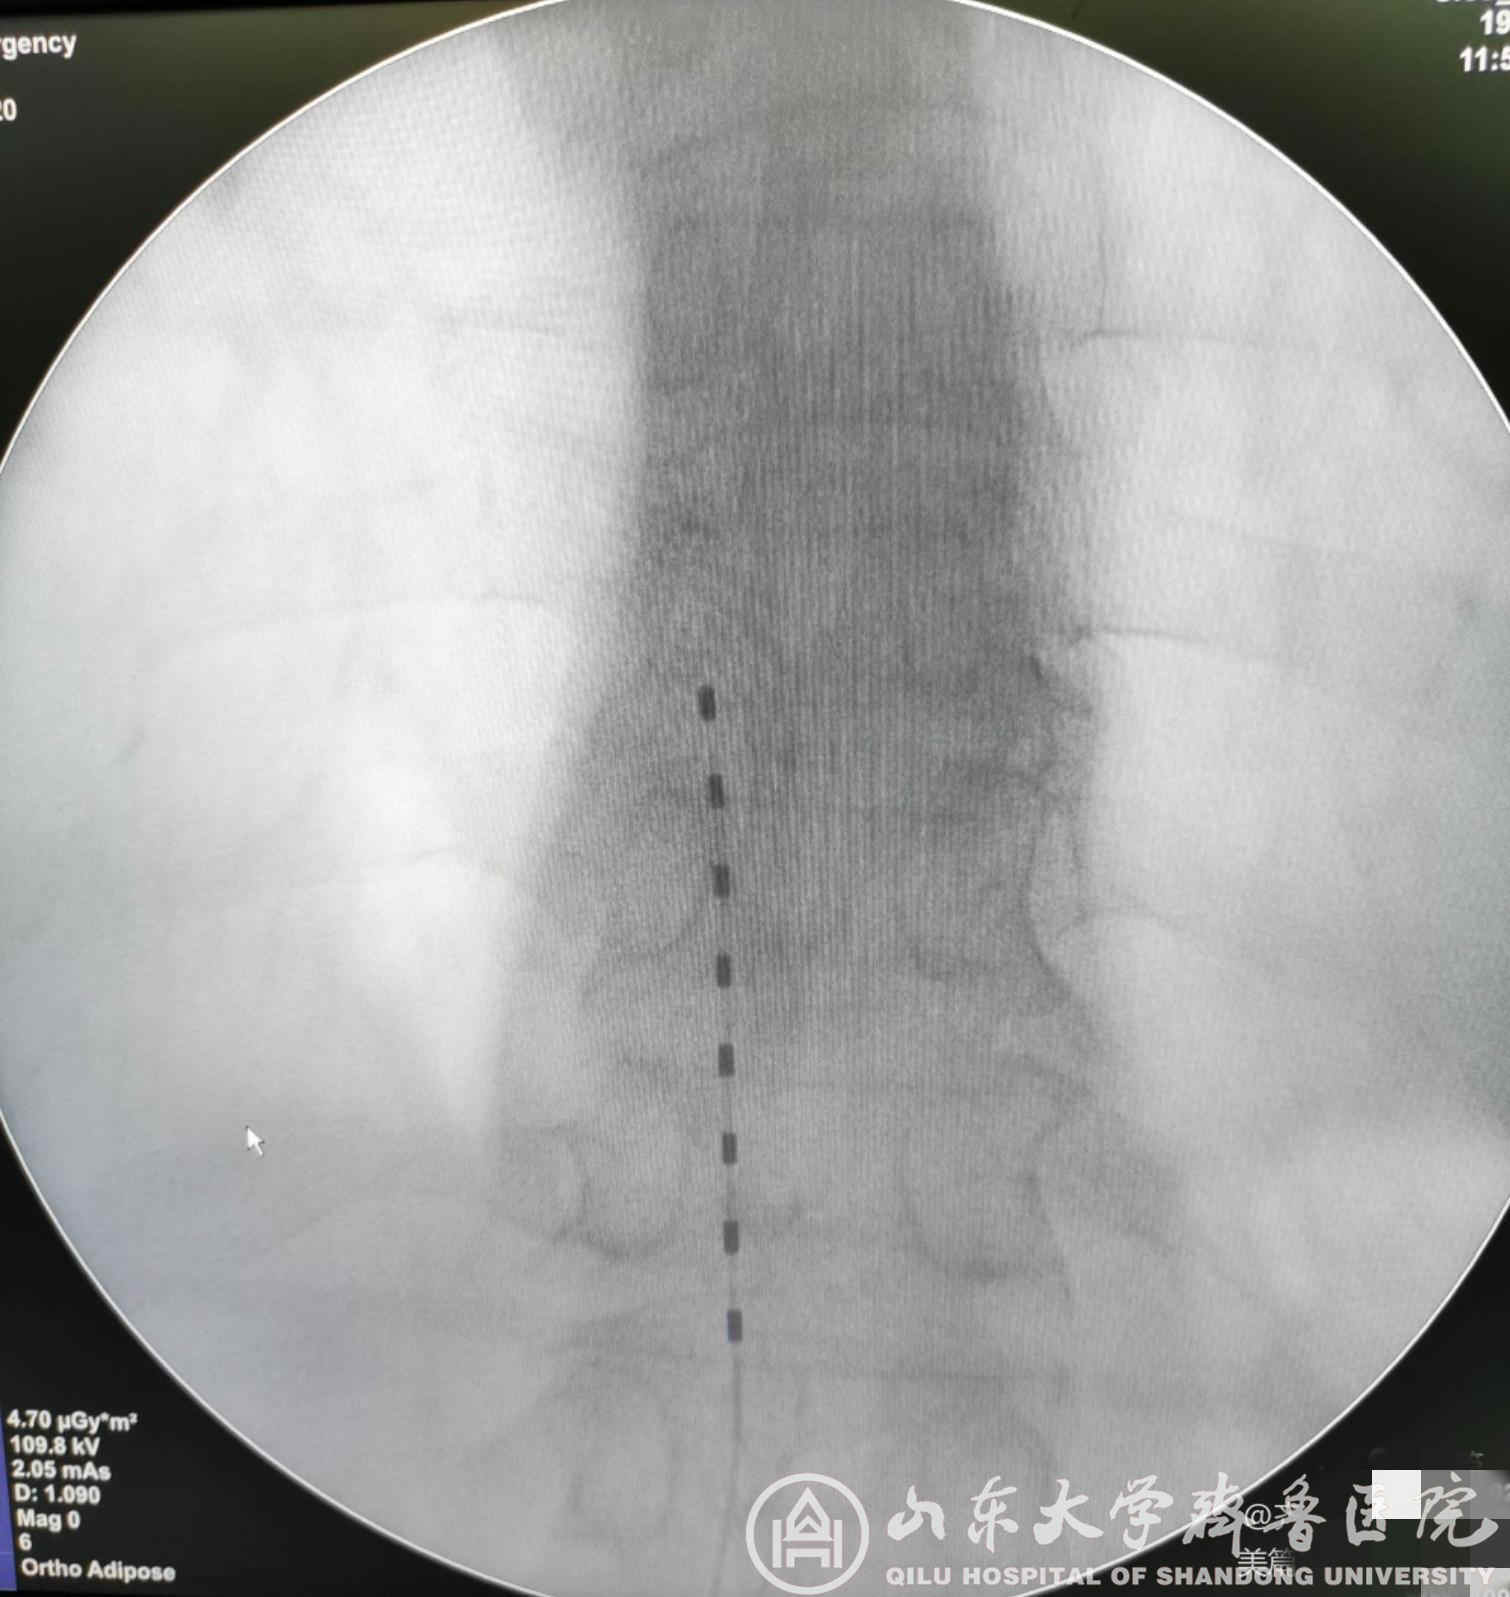

图1.带状疱疹性神经痛患者术后X线检查电极位置良好